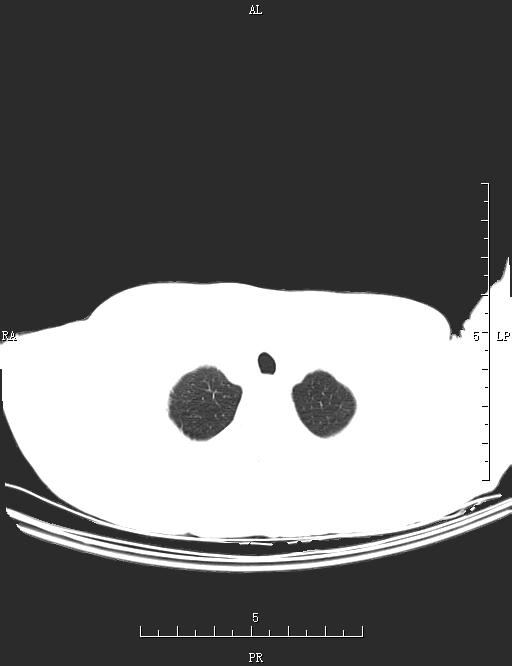

CT53056:胸部CT

男,69岁,胸痛1月余。

右上肺及近胸膜下可见多发小圆形低密度透亮影伴少许淡薄模糊影。左下肺可见线条状及小三角形不张影。考虑:右上肺多发性肺大泡伴肺气囊肿并感染,左下肺盘状不张。

右肺多发肺大泡伴肺气囊肿形成 合并少许感染。另:左侧肺底部盘状肺不张。